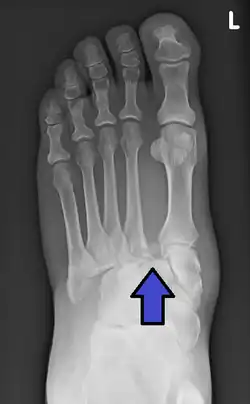

An X-ray of a Lisfranc injury

In a high energy injury to the midfoot, such as a fall from a height or a motor vehicle accident, the diagnosis of a Lisfranc injury should, in theory at least, pose less of a challenge. There will be deformity of the midfoot and X-ray abnormalities should be obvious. Further, the nature of the injury will create heightened clinical suspicion and there may even be disruption of the overlying skin and compromise of the blood supply. Typical X-ray findings would include a gap between the base of the first and second toes.[8] The diagnosis becomes more challenging in the case of low energy incidents, such as might occur with a twisting injury on the racquetball court, or when an American Football lineman is forced back upon a foot that is already in a fully plantar flexed position. Then, there may only be complaint of inability to bear weight and some mild swelling of the forefoot or midfoot. Bruising of the arch has been described as diagnostic in these circumstances but may well be absent.[9] Typically, conventional radiography of the foot is utilized with standard non-weight bearing views, supplemented by weight-bearing views which may demonstrate widening of the interval between the first and second toes, if the initial views fail to show abnormality. Unfortunately, radiographs in such circumstances have a sensitivity of 50% when non-weight bearing and 85% when weight-bearing, meaning that they will appear normal in 15% of cases where a Lisfranc injury actually exists.[10] In the case of apparently normal x-rays, if clinical suspicion remains, advanced imaging such as magnetic resonance imaging (MRI) or computed tomography (CT scan) is a logical next step.[11]